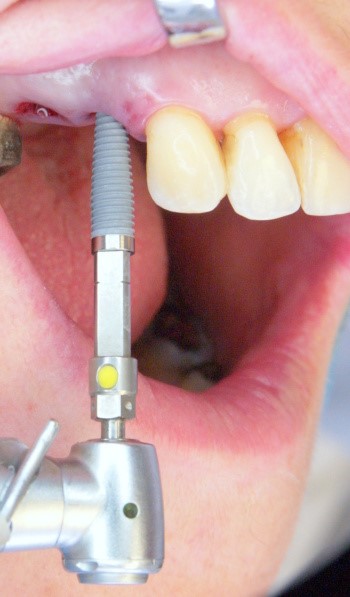

Пациентка обратилась с кариесом корня 14 зуба и 15 зуба с разрушением коронковой части зуба, ранее леченного с установкой анкерного штифта.

Имплантация 14, 15 зуба с циркониевой коронкой на импланте: